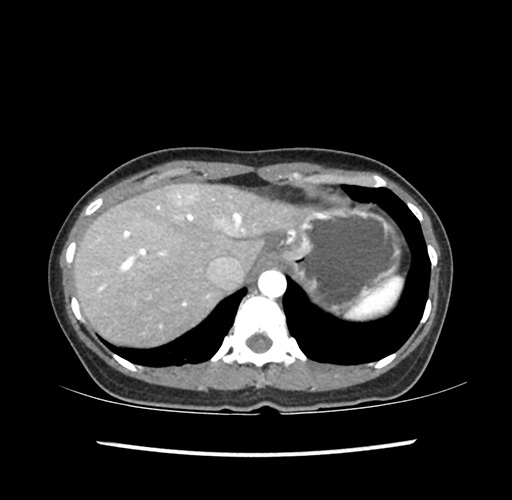

Left lateral sectionectomy [case 12]

Imaging Analysis

Look through the patient's CT scan to identify any areas of concern for the necessary procedure.

Based on your CT findings, which issue(s) would give reason for "planned slowing down moment(s)" in this case?

Considering a standard left lateral sectionectomy procedure, what step(s) of the operation would you do differently in this case ?